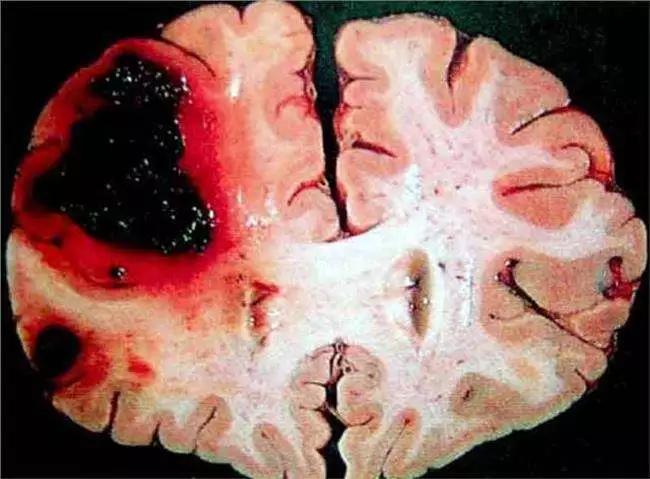

腦出血是急性出血性腦卒中,是指非外傷性腦實質(zhì)內(nèi)血管破裂,引起的出血。臨床上80%左右的腦出血,是高血壓性腦出血,其他病因還包括,腦動脈瘤、煙霧病、腦血管畸形。那么腦出血是什么原因?qū)е碌哪?

導致腦出血的原因是有很多的,但是高血壓病是最重要的可變性危險因素。高血壓是腦出血最為主要的原因,腦出血的發(fā)生是在高血壓和動脈硬化的基礎(chǔ)上,腦內(nèi)穿通動脈上可以形成許多微動脈瘤,主要分布在大腦基底節(jié)竇紋動脈,橋腦,大腦白質(zhì)和小腦,當血壓驟然升高的時候微動脈瘤可能會迅速破裂而導致出血,或者由于長期的高血壓,對腦實質(zhì)內(nèi)穿通動脈管壁的內(nèi)膜發(fā)生玻璃樣變性或者纖維樣壞死,在血壓或者血流急劇發(fā)生變化的時候,非常容易破裂出血。